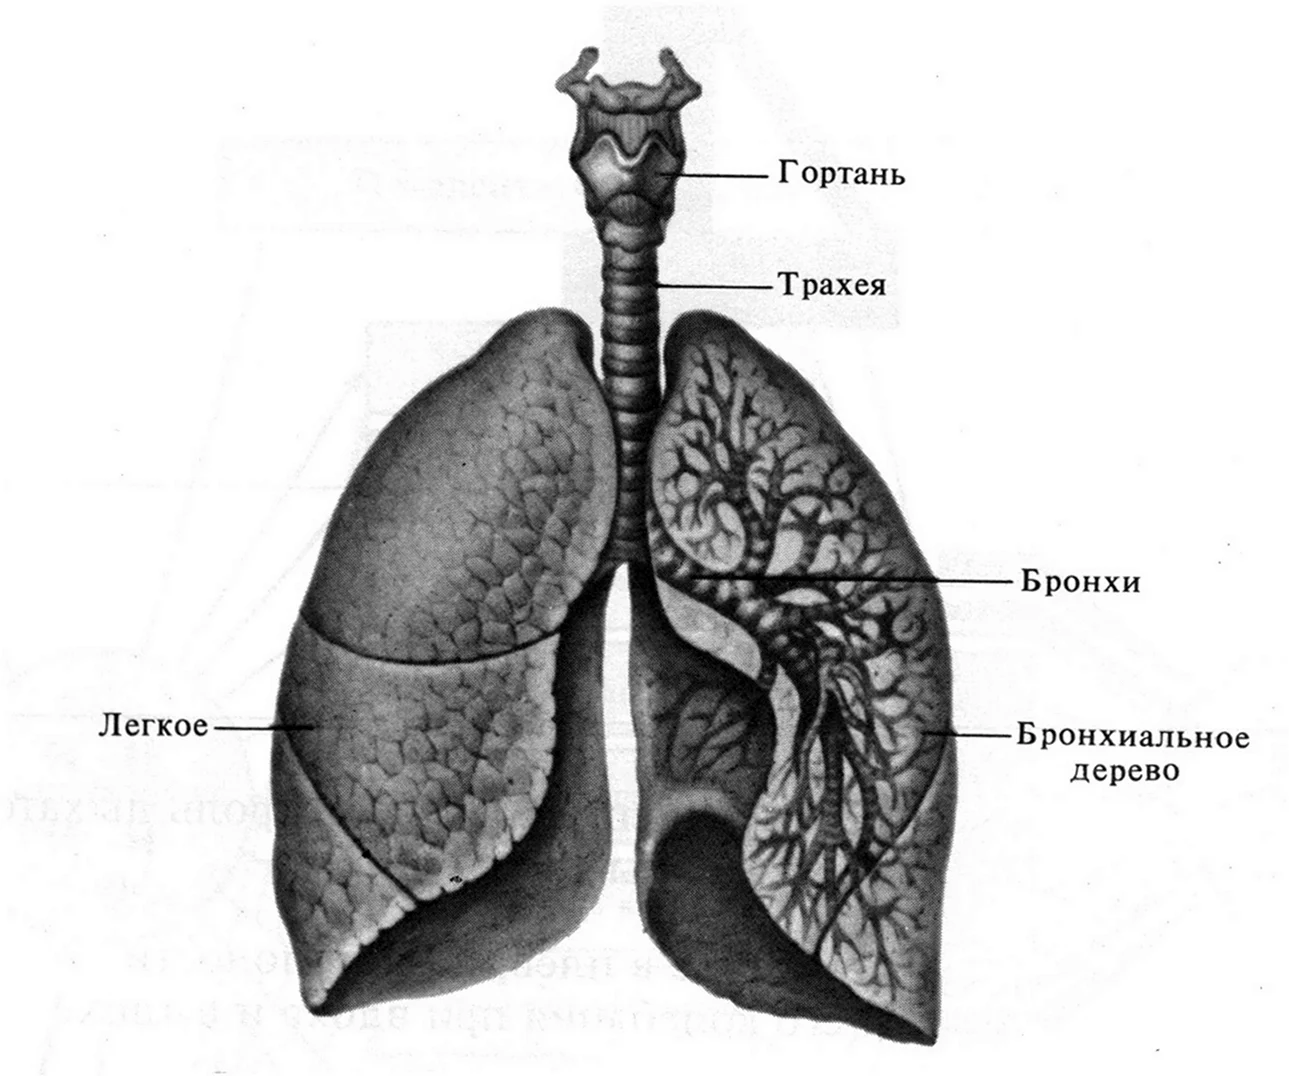

Таинство дыхания: глубокий взгляд на легкие человека в картинках

Раздел: Снимки-откровения